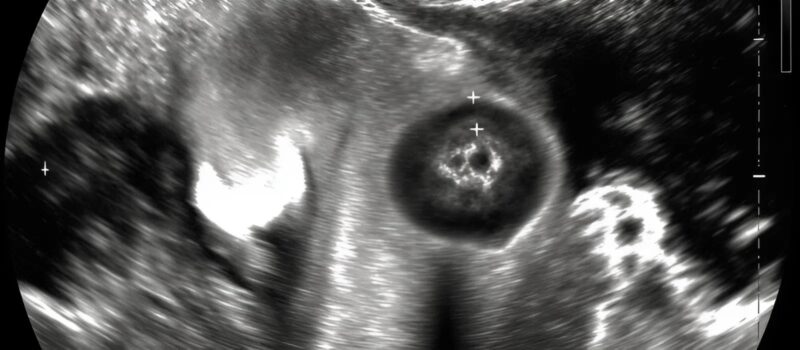

An ultrasound revealed something unexpected. The doctor’s face shifted, his eyes locking on mine. Then he said a single word that made my stomach drop: “Emergency.” 😳

The ultrasound brought clarity. The doctor smiled with reassurance and said, “We can help her with a small procedure today.” 😌⚡ What we thought were minor backaches were signals of something that could now be corrected easily. A small kidney stone had traveled and caused her discomfort 🪨.